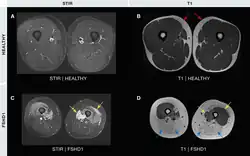

Medical imaging (CT and MRI) have shown muscle involvement not readily apparent otherwise[37]

- A single MRI study shows the teres major muscle to be commonly affected.[38]

- The semimembranosus muscle, part of the hamstrings, is commonly affected,[25][84][85] deemed by one author to be "the most frequently and severely affected muscle."[2]

- Of the quadriceps muscles, the rectus femoris is preferentially affected[84]

- Of the gastrocnemius, the medial section is preferentially affected;[84][85]

- The iliopsoas, a hip flexor muscle, is very often spared.[85][2]

- Magnetic resonance imaging (MRI) is sensitive for detecting muscle damage, even in mild cases. T1-weighted MRI imaging can visualize fatty infiltration of muscles, and T2-weighted MRI imaging can visualize muscle edema. MRI can help differentiate FSHD from other muscle diseases based on the pattern of muscles involved, directing genetic testing.[37][38]